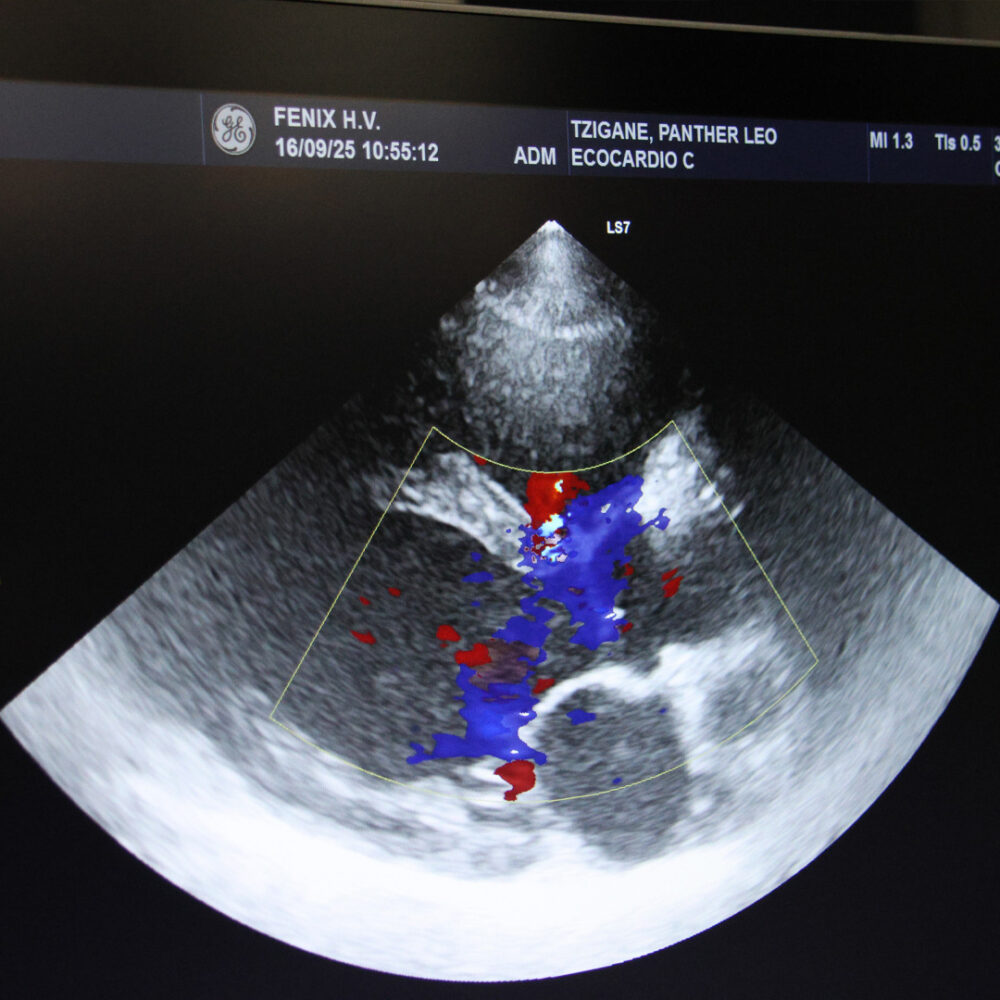

echo hart

Een echocardiogram van Tzigane's hart.

De dierenartsen onderzochten Tzigane’s hart met een echocardiogram. Hij bleek inderdaad een lichte hartruis te hebben. Tot onze verrassing was de conditie van zijn hart beter dan we dachten. Er was slechts een kleine vegroting en een onschuldige hartruis, die meestal geen problemen veroorzaakt bij dieren. Daarom besloten we zijn hartmedicatie stop te zetten.